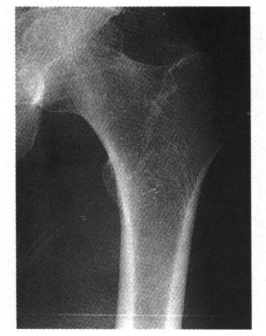

2.股骨大小粗隆的骨化核可为多个,形态可不规则(图2)。

图2 股骨大粗隆骨化核边缘不规则